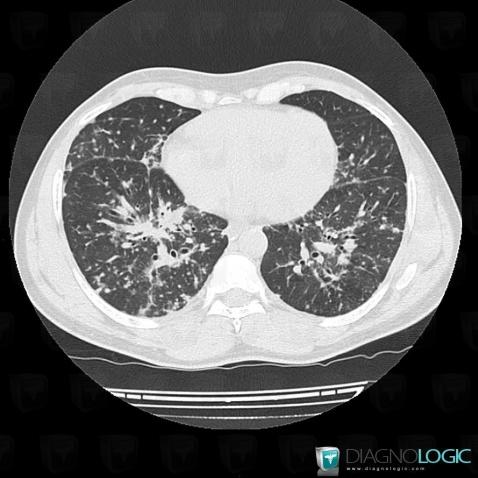

Sarcoïdose, Parenchyme pulmonaire, Scanner

Voici les informations spécifiques à l'image clé ci dessus:

- Diagnostic Sarcoïdose, Localisation(s) Parenchyme pulmonaire, comportant les gammes Epaississement péri broncho vasculaire / Epaississement septal irrégulier